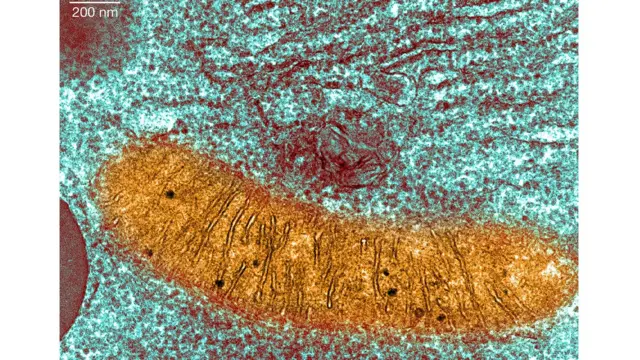

माइटोकन्ड्रिआ हाम्रो कोषहरूभित्र रहेका विशेष तत्त्वहरू हुन् जसले खानेकुराबाट पाइने ऊर्जालाई हाम्रो शरीरका लागि आवश्यक शक्तिमा बदल्छन्। तर तिनीहरूमा रोग निम्त्याउने तत्त्वले प्रवेश पाएको अवस्थामा नियमित काम गर्न सक्दैनन्।